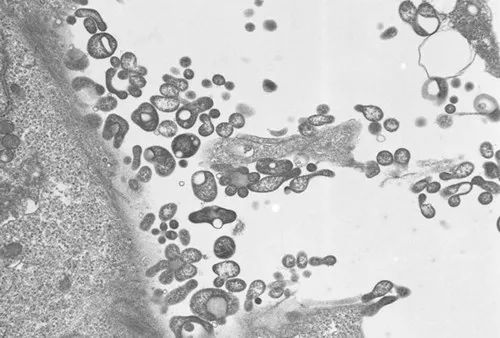

别尔德克雷切夫说,针对俄罗斯近来出现的咳血病例,世卫组织磋议了俄罗斯关系机构。俄方按世卫组织条款提供了5例在莫斯科和莫斯科州登记的病例数据。经实践室接洽阐发,这5例病例所患疾病是支原体感染引起的肺炎,不是新病毒感染。